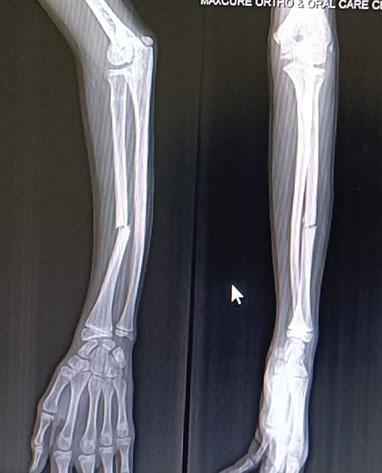

Phase 1: Meticulous Closed Reduction

The procedure began under general anesthesia to ensure complete muscle relaxation. We used slow, sustained traction and manipulation to correct angulation and, critically, rotational malalignment. We confirmed the reduction instantly using fluoroscopy (real-time X-ray imaging).

Phase 2: The Above-Elbow Cast in Extension Technique

Traditional casting often fails to neutralize the strong deforming forces in this injury. We placed the elbow in near-full extension (straightened) to put key muscles on slack or tension. This position, combined with specific rotational alignment, helps to “lock” the reduction.